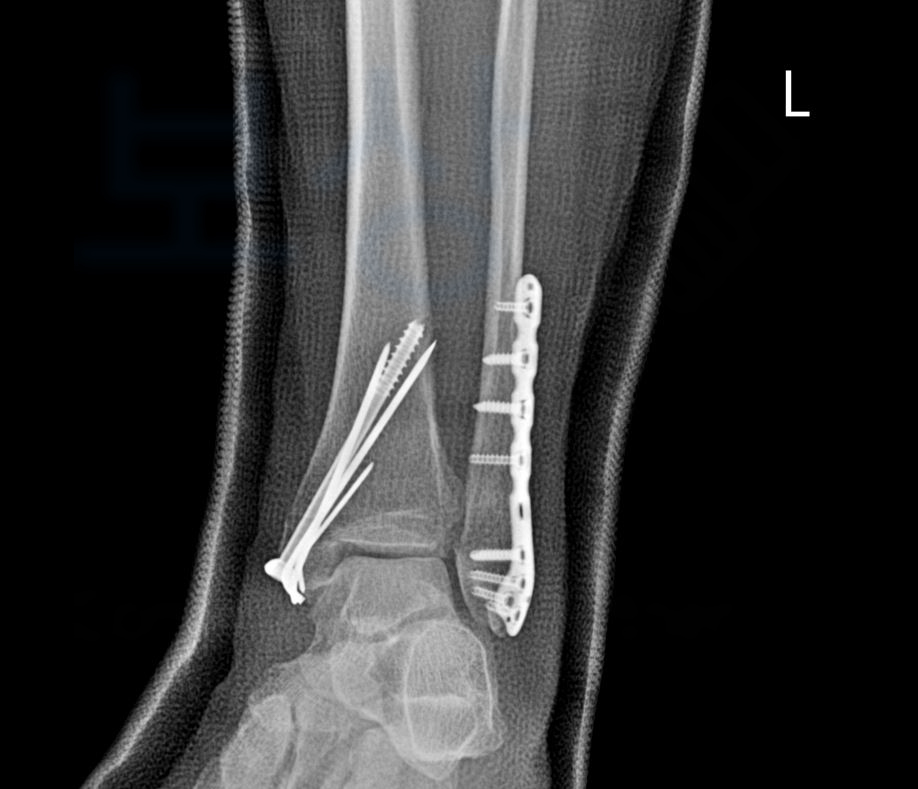

Lt. ankle pain 왼쪽 발목 통증 정밀검사를 받아보니 아래의 사진처럼 흔히 말하는 발목의 복숭아뼈가 골절되어 수술이 불가피 했습니다.

좌측 족관절의 외복사골절, 관혈적 정복 및 금속판 내고정술

의뢰인읜 양측의 복사골절 즉 외복사, 내복사 또는 양과 골절 수술받아 6주 이상의 입원 및 재활치료를 받아야 했죠. 의뢰인은 보상파트너의 도움을 받아 가입하신 보험증권에서 상해후유장해 항목을 찾으셨습니다.